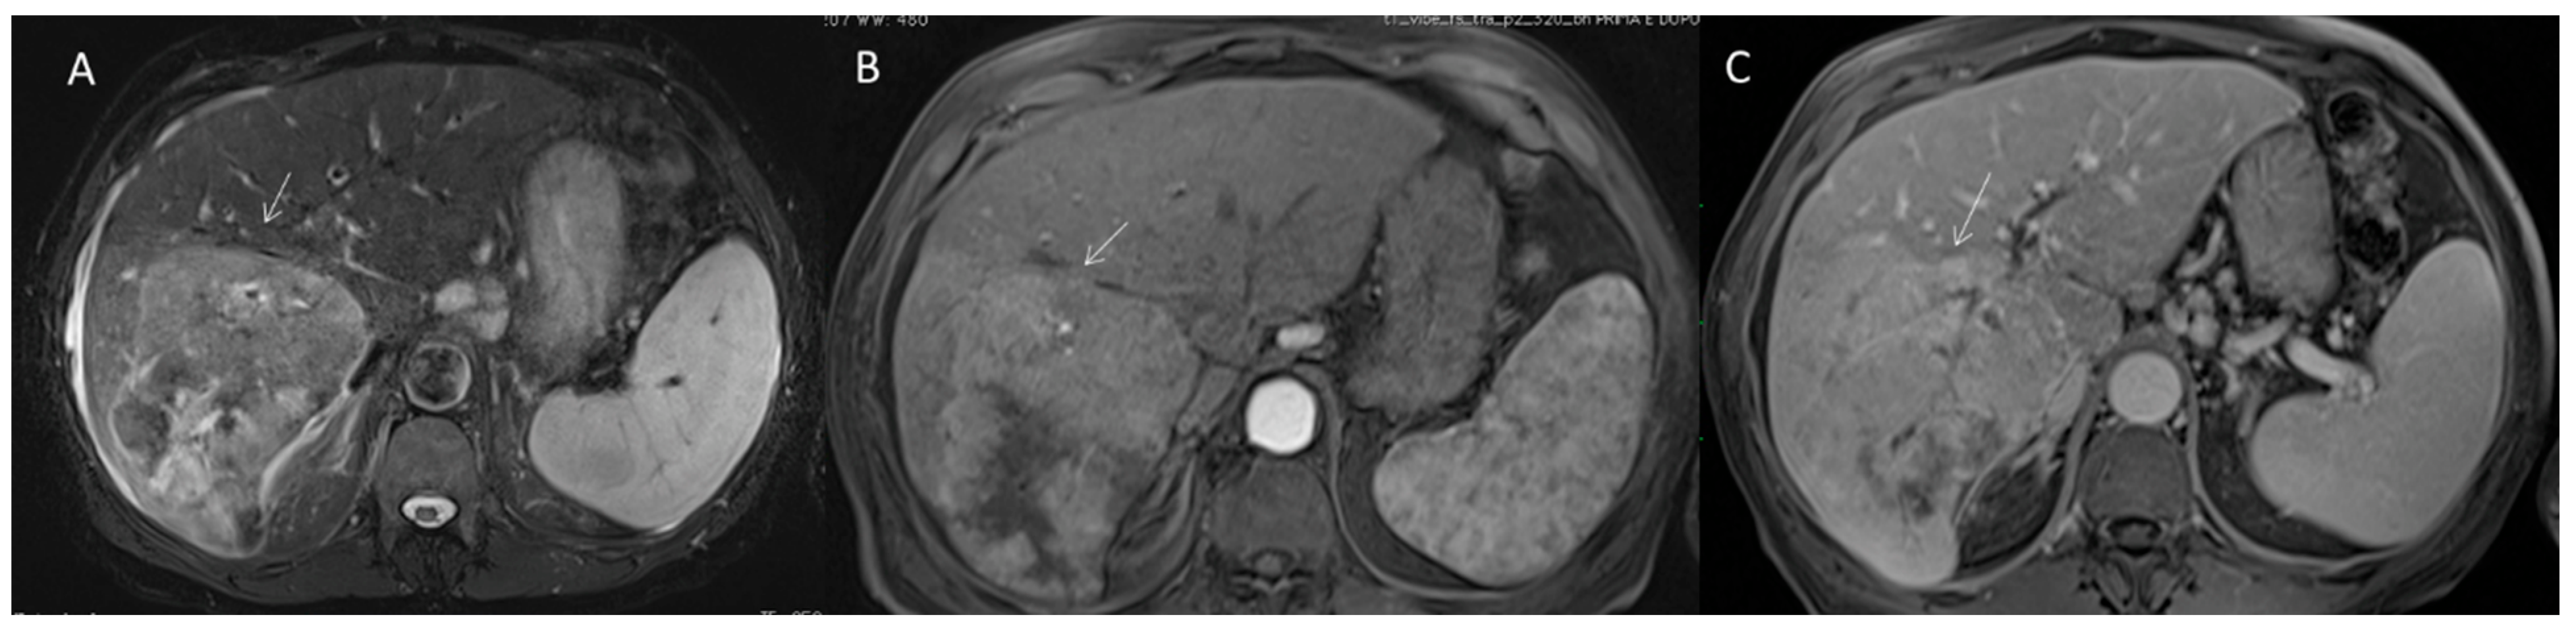

2.2.5. LR-M Category

2.2. CT/MRI LI-RADS

2.2.3. HCC Diagnosis